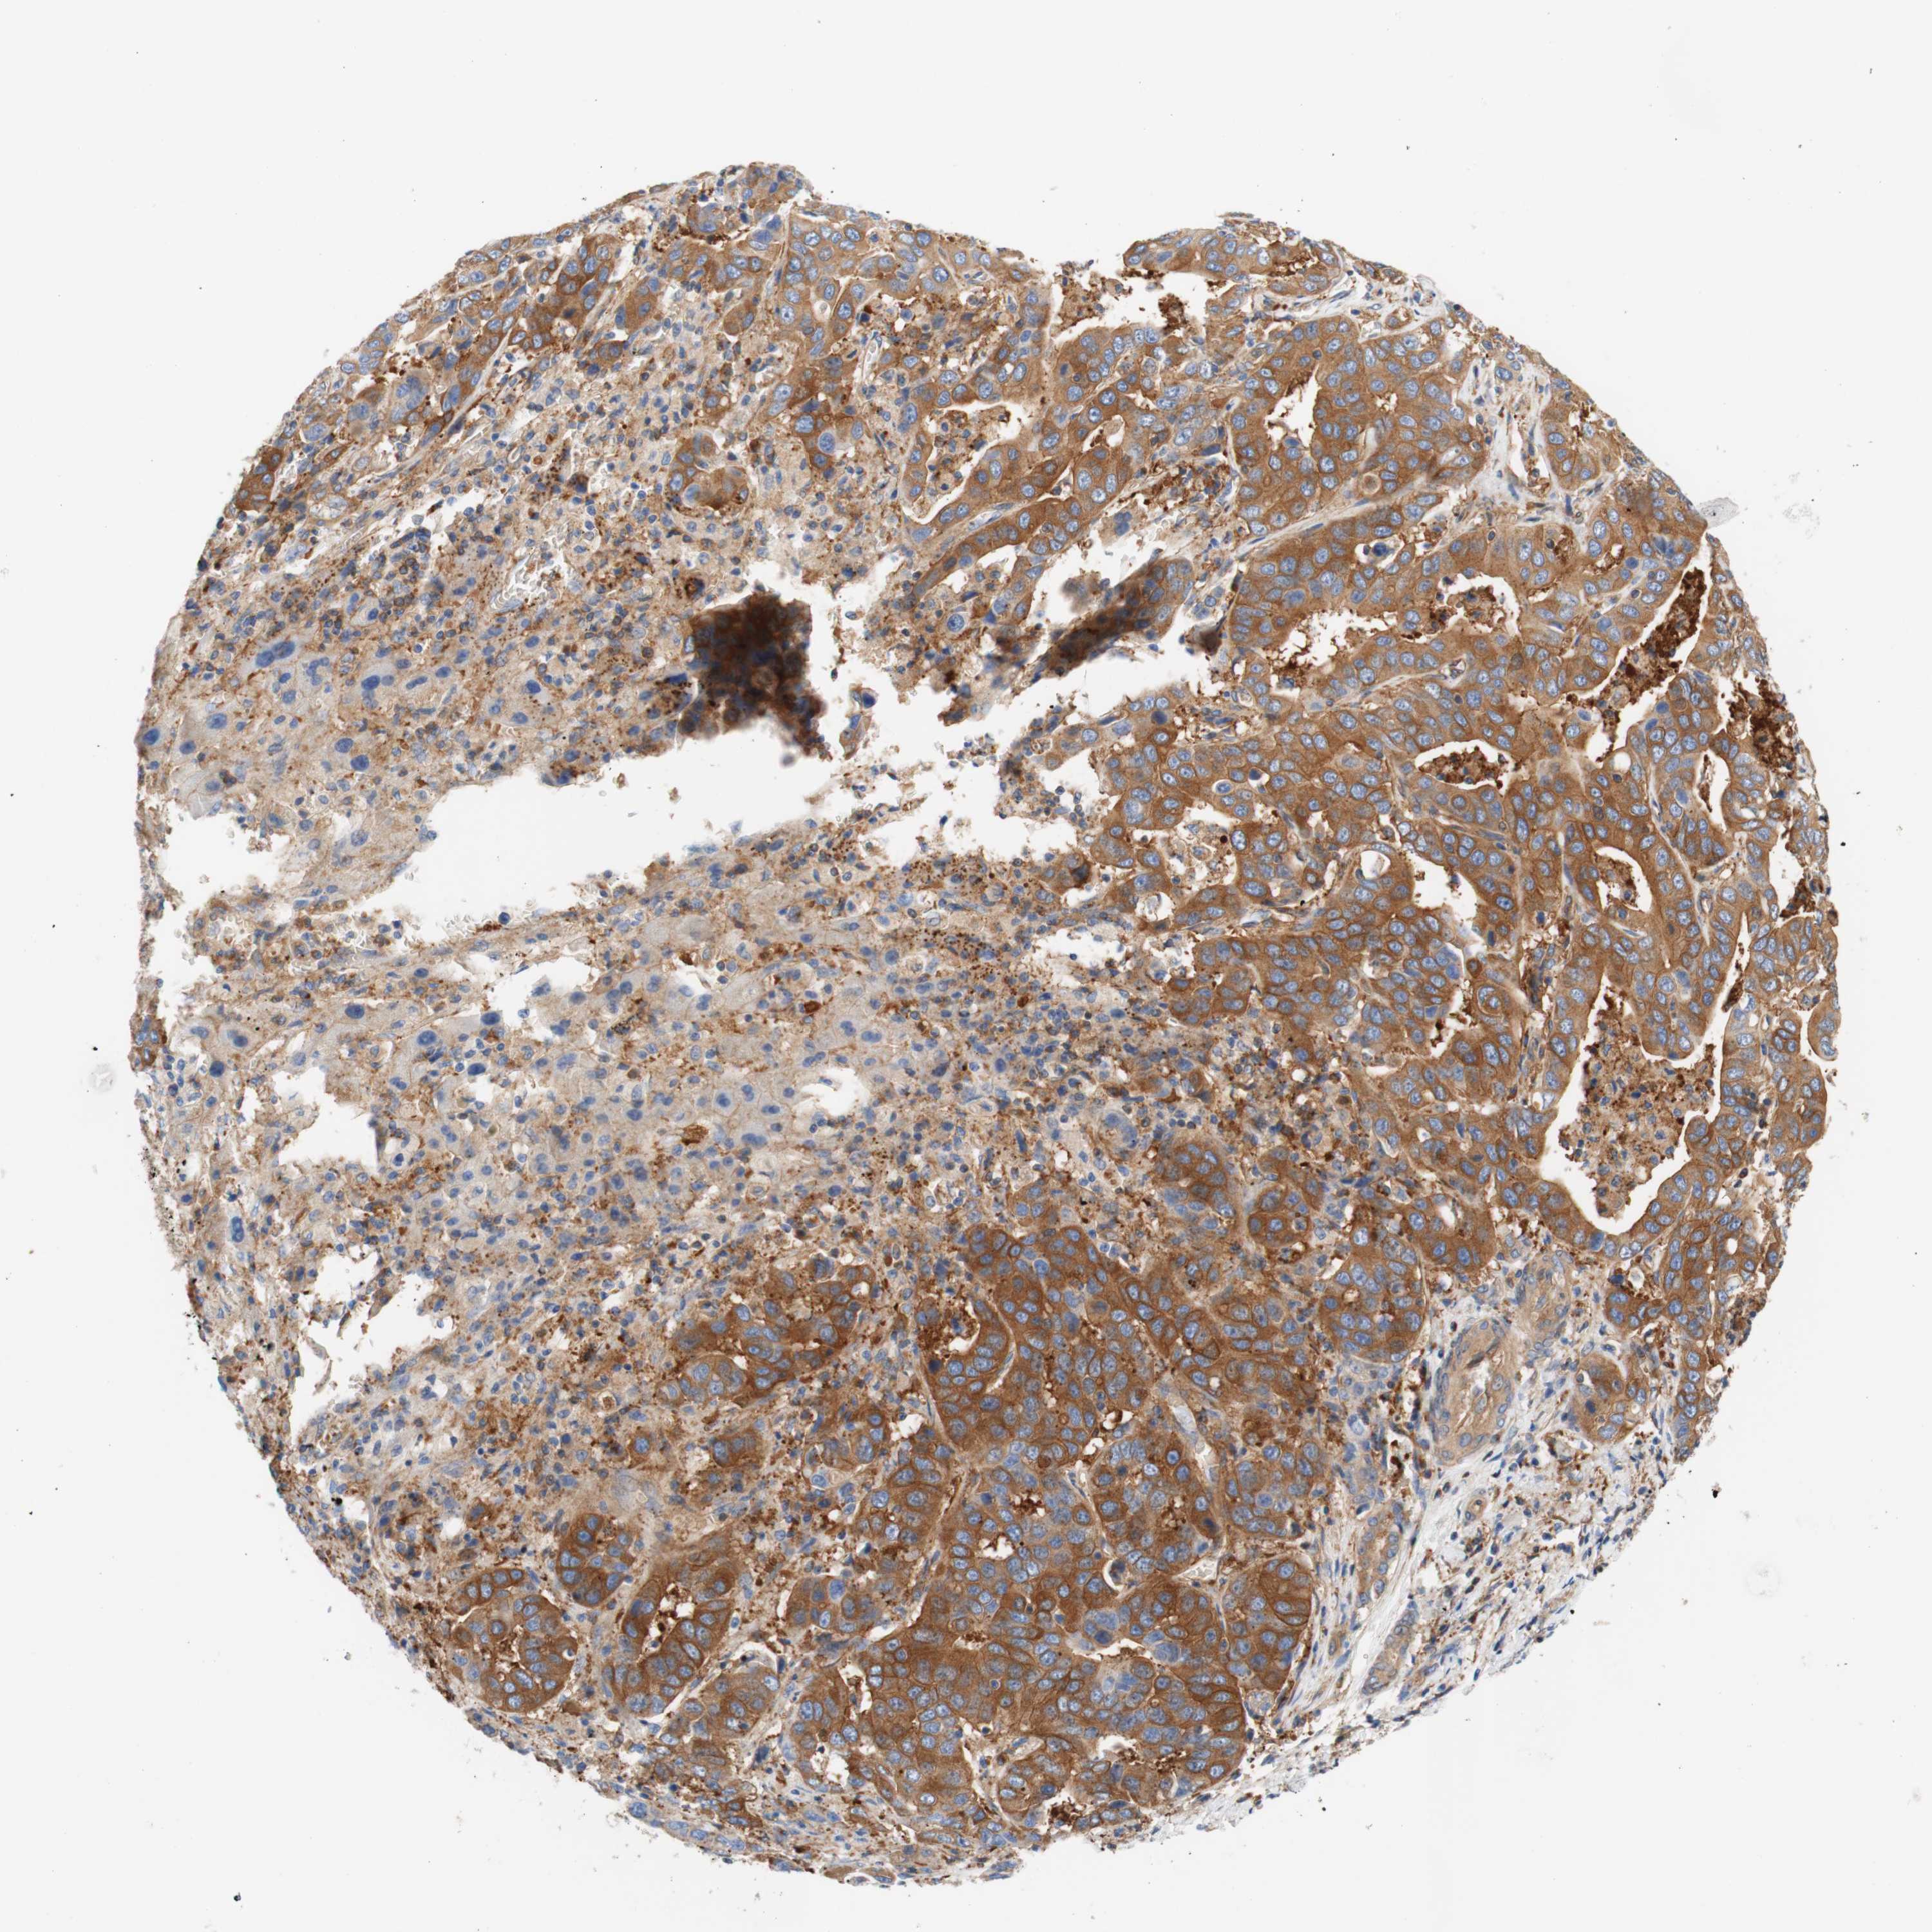

LIVER CANCER - Protein expressioni

A mouse-over function shows sample information and annotation data. Click on an image to view it in a full screen mode. Samples can be filtered based on level of antibody staining by selecting one or several of the following categories: high, medium, low and not detected. The assay and annotation is described here.

Note that samples used for immunohistochemistry by the Human Protein Atlas do not correspond to samples in the TCGA dataset.

Antibody stainingi

Antibody staining in the annotated cell types in the current human tissue is reported as not detected, low, medium, or high, based on conventional immunohistochemistry profiling in selected tissues. This score is based on the combination of the staining intensity and fraction of stained cells.

Each image is clickable and will lead to virtual microscopy that enables deeper exploration of all samples and also displays staining intensity scores, fraction scores and subcellular localization as well as patient and tissue information for each sample.

Antibody HPA010961

Antibody HPA011419

Staining

High

Medium

Low

Not detected

Intensity

Strong

Moderate

Weak

Negative

Quantity

>75%

75%-25%

<25%

None

Location

Nuclear

Cytoplasmic/membranous

Cytoplasmic/membranous,nuclear

Cholangiocarcinoma

Carcinoma, Hepatocellular, NOS